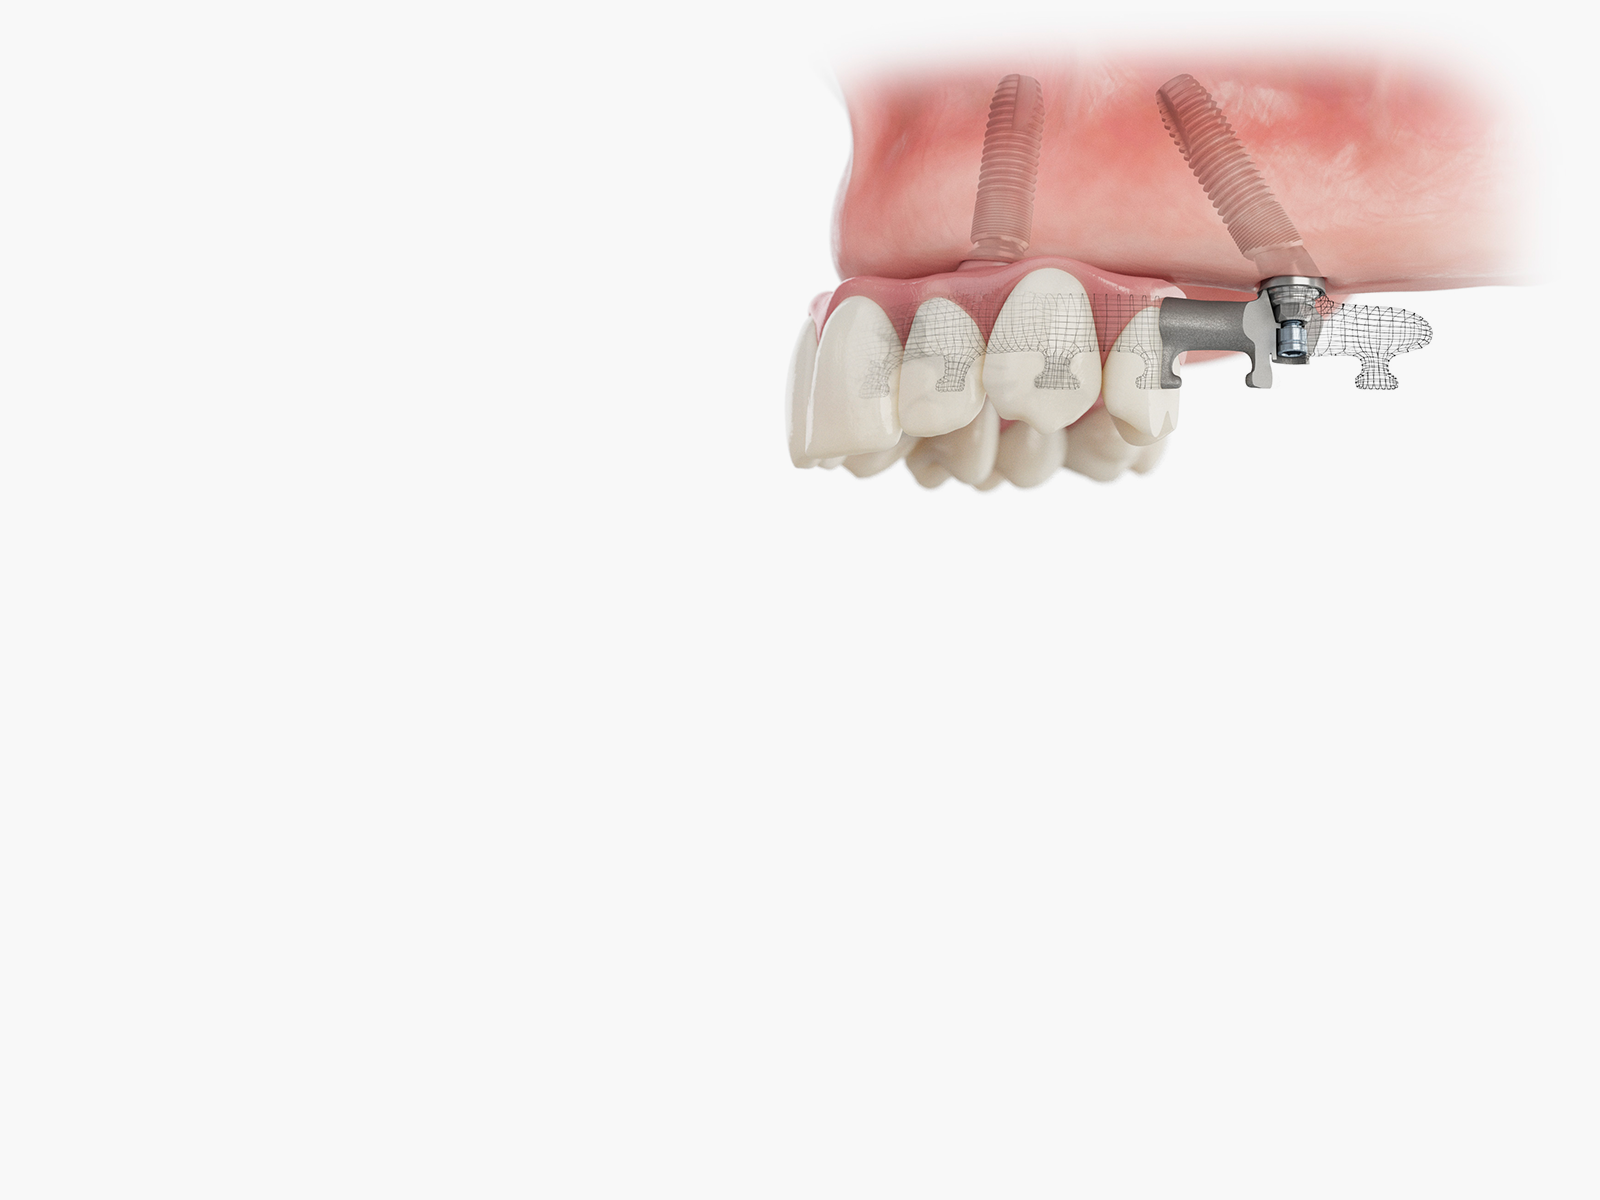

Thanks to digital dentistry, clinicians have access to groundbreaking solutions, enabling them to plan and execute all-inclusive dental treatments with unparalleled accuracy and effectiveness. This free online aligner course series helps dental professionals become more confident and comfortable using clear aligner therapy (CAT), which has become a popular choice for patients looking for a less intrusive orthodontic option. In this series, learners will gain an understanding of the biomechanics of therapeutic tooth movement, efficient treatment methodologies, and how to diagnose and treat cases.

Foundational

These beginner-level courses are ideal for those new to clear aligner therapy or looking to refresh their knowledge. These two courses will familiarize participants with the biomechanics involved in therapeutic teeth movement and educate them on the advantages of using aligners to correct misaligned teeth. By the end of the Foundational courses, you will have a concrete understanding of the basics of aligners, allowing you to confidently move forward to our intermediate-level series, the Procedure-Based courses.

Procedure-Based

The intermediate-level courses are ideal for clinicians with an established understanding of the basics of clear aligner therapy or those looking to refine their skills. These five interactive courses are designed to provide clinicians with a comprehensive understanding of identifying and treating aligner case types efficiently and predictably. At the end of the Procedure-Based courses, you are encouraged to move forward to our advanced courses, the Mastery courses.

Mastery

These two advanced-level courses are ideal for experienced clinicians with an established understanding of clear aligner therapy. These interactive courses will teach clinicians how to diagnose and treat more complex case types, including interdisciplinary cases. Participants will also learn about auxiliaries and adjuncts to control root and bodily movements better. By the end of the Mastery courses, participants will have the confidence to incorporate CAT into their practice.